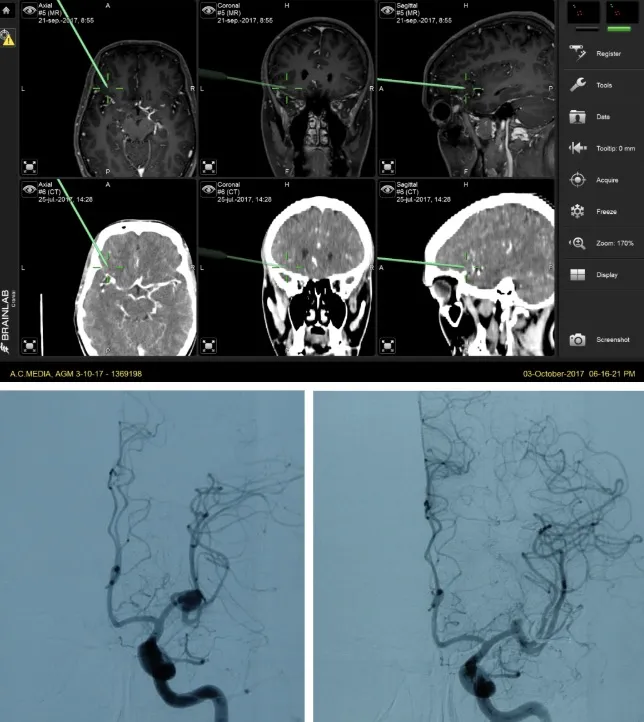

El neuronavegador es otra herramienta fundamental que permite localizar con absoluta precisión la posición del aneurisma y planificar la ruta quirúrgica más segura para acceder a él, integrando las imágenes de TAC y resonancia magnética preoperatorias con la realidad anatómica del paciente durante la intervención.

Una vez confirmada la hemorragia, es necesario identificar el aneurisma responsable. Para ello se emplean la angio-TAC (TAC con contraste vascular) y el estudio angiográfico cerebral (arteriografía), que no solo permiten localizar y caracterizar el aneurisma antes de la intervención, sino que también sirven para comprobar que el aneurisma se ha cerrado correctamente tras el tratamiento.

El objetivo terapéutico fundamental es el cierre precoz del aneurisma para prevenir el resangrado. Existen dos modalidades principales de tratamiento:

- Embolización endovascular: se introduce un catéter a través de una arteria periférica hasta llegar al aneurisma, donde se depositan espirales (coils) u otros materiales que rellenan el saco aneurismático y lo excluyen de la circulación.

- Cirugía (clipaje): mediante una intervención neuroquirúrgica se coloca un clip metálico en el cuello del aneurisma para cerrarlo definitivamente e impedir que la sangre entre en su interior.